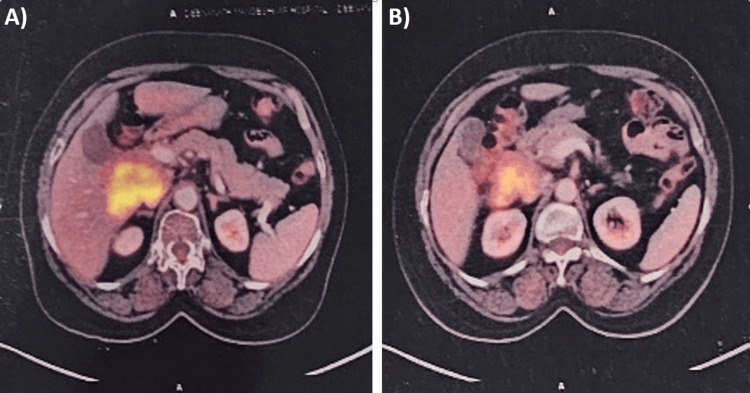

Imaging studies, including ultrasound and CT scan, identified a mass in the caudate lobe of the liver with dilated intrahepatic bile ducts (Figures 1A, 1B), encroaching on the duodenum (Figure 1C), and CBD (Figure 1D), causing partial gastric outlet obstruction and obstructive jaundice. PET-CT (Figure 2) confirmed persistent abnormally increased fluorodeoxyglucose (FDG) uptake in a hypo-enhancing lesion at the post-operative site in the caudate region, infiltrating the first and second parts of the duodenum with luminal narrowing and showing effacement of fat planes with the portal vein and inferior vena cava (IVC). The lesion also abutted the head of the pancreas with suspicious loss of the fat plane, measuring approximately 66 x 68 mm (SUVmax 14.8). Persistent abnormally increased FDG uptake was also noted in a hypo-enhancing lesion involving the splenic parenchyma adjacent to the hilum, measuring 28 x 20 mm (SUVmax 4.2). Upper GI endoscopy with side view scope (esophagogastroduodenoscopy (EGD)) revealed external compression on the duodenum with D1 mucosa edematous, erythematous with superficial ulceration causing D1 and D2 narrowing, corroborating the imaging findings of partial gastric outlet obstruction (Figure 3).